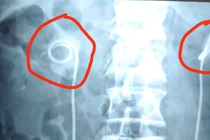

Để sonde JJ quá 2 năm, sỏi bám vòng quanh gây thận ứ nước, nguy cơ ngừng tim

Theo chỉ định, sonde JJ cần được rút ra trong vòng 3 tháng nhưng thấy sức khỏe bình thường, ông T. không đi khám và gặp biến chứng đe dọa tính mạng.